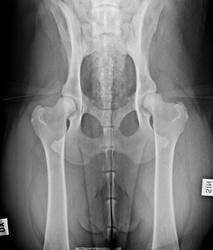

Lonkkaniveldysplasia (HD)

Lonkkaniveldysplasia on lonkkanivelen kehityshäiriö, jossa nivel ei ole rakenteeltaan täysin normaali. Oireet vaihtelevat lievästä jäykkyydestä aina selvään ontumiseen. Kaikki dysplasiaa sairastavat koirat eivät ole oireisia. Perinnöllisten tekijöiden lisäksi lonkkanivelen terveyteen vaikuttavat muun muassa kasvuajan kuormitus, lihaskunto ja painonhallinta.